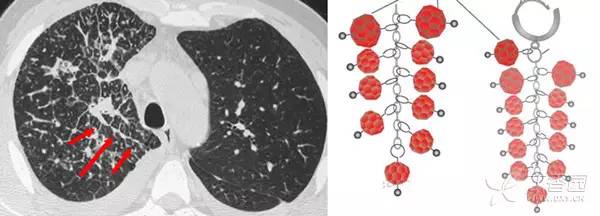

树芽征是指病变累及细支气管时,由于炎性渗出物或分泌物堵塞细支气管,CT 表现为小叶中心分枝状线影和与其相连的细支气管横断面结节影,状如春天里挂满枝芽的「树」,即「树芽征」。

CT 不能显示直径小于 2 mm 支气管,故正常小叶支气管 CT 扫描时不显示,但当小叶支气管发生病变时,CT 就可以显示出来。

树芽征的相关疾病有:肺支气管的感染性病变、免疫性疾病如变应性支气管肺型曲霉菌病、先天性疾病如囊性肺纤维化及纤毛运动异常综合征(Dyskinetic’s 综合征)、吸人刺激性物质等。